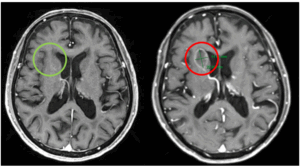

CASE LÂM SÀNG Điều trị bệnh nhân ung thư phổi di căn não giai đoạn muộn tại Trung tâm Y học hạt nhân và Ung bướu-Bệnh viện Bạch Mai PGS.TS. Phạm Cẩm Phương1,2, GS.TS. Mai Trọng Khoa1,2, Sinh viên Nguyễn Thị Hải Anh,2 1Trung tâm Y học hạt nhân và...